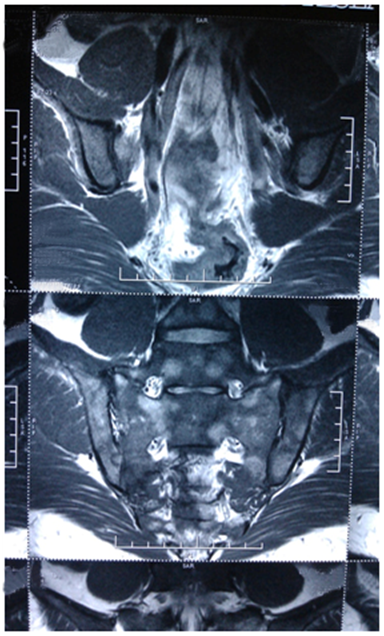

Patient’s complete blood count and peripheral smear was normal. The results of urine culture, blood culture and serology of viruses including EBV, CMV, hepatitis B, C and HIV were negative. Erythrocyte sedimentation rate: 68mm/h, C-reactive protein: 24mg/L (normal<5). HLAB27 was negative and mantaux was 14mm. Blood TB PCR, TB quantiferon Gold test and serology for Brucella was negative. X rays of the spine, pelvis and sacro-iliac joints were normal. Ophthalmological and skin examination was normal. MRI of the Sacro-iliac joint revealed diffuse patchy marrow edema in the bilateral sacro-iliac joints (Figure 1) involving bilateral sacral ala and juxta articular iliac bones and associated with diffuse patchy marrow edema in the vertebral bodies from thoracic to sacrum vertebrae. There was mild reduction of joint space in the bilateral sacro-iliac joint inferiorly with erosive changes in the articular surface of iliac aspect of right sacro-iliacjoint. MRI of whole spine revealed diffuse patchy marrow edema in the vertebral bodies (Figure 2). Bone marrow examination was essentially normal.

Figure 2 MRI of whole spine revealed diffuse patchy marrow edema in the vertebral bodies.